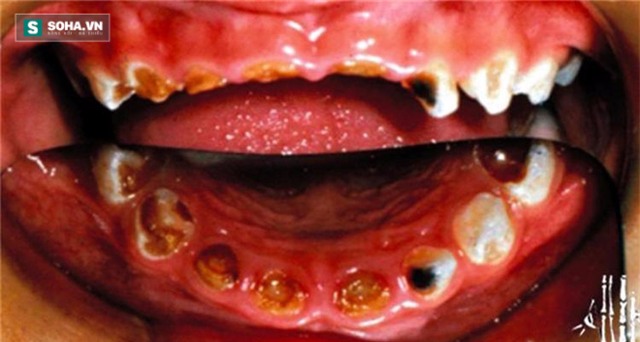

Bác sĩ đã không khỏi giật mình khi bé vừa mở miệng ra. Ông nói rằng cậu bé chẳng khác gì một ông già tí hon không còn răng, miệng lổn nhổn chân răng đen nhẻm và hơi thở có mùi.

Thông thường, trẻ em có khoảng 20 chiếc răng sữa. Sau khi kiểm tra sơ bộ, bác sĩ cho biết Quân Quân đã có 8 chiếc răng thối hoàn toàn chỉ còn chân răng bên trong.

Cùng lúc đó, 6 chiếc răng khác cũng bị biến dạng, vừa đen vừa vàng, sứt mẻ, không còn có thể nhận dạng được.

Trước tình trạng khủng khiếp như vậy, thiếu răng không chỉ mất thẩm mĩ, ảnh hưởng sức khỏe, mà ngay cả phát âm cũng không còn được rõ ràng.